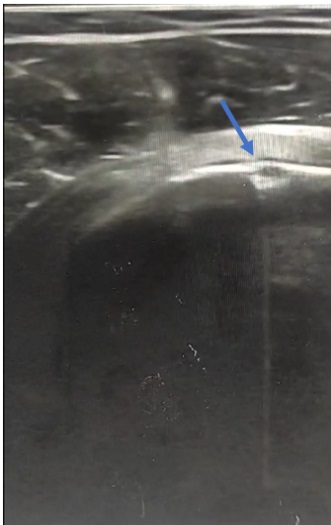

• Se realizó una ecografía, en la que se apreció una solución de continuidad en la cortical del húmero que hizo pensar en una avulsión del tendón del músculo subescapular.

• Juicio clínico: avulsión del tendón del músculo subescapular del hombro derecho.